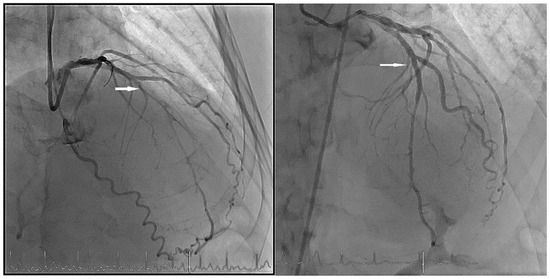

When performing revascularisation of a chronic total occlusion, contralateral injection is essential to visualise the distal bed of the occluded vessel, adding to procedural success. Here we describe a case of antegrade recanalisation of a left anter...